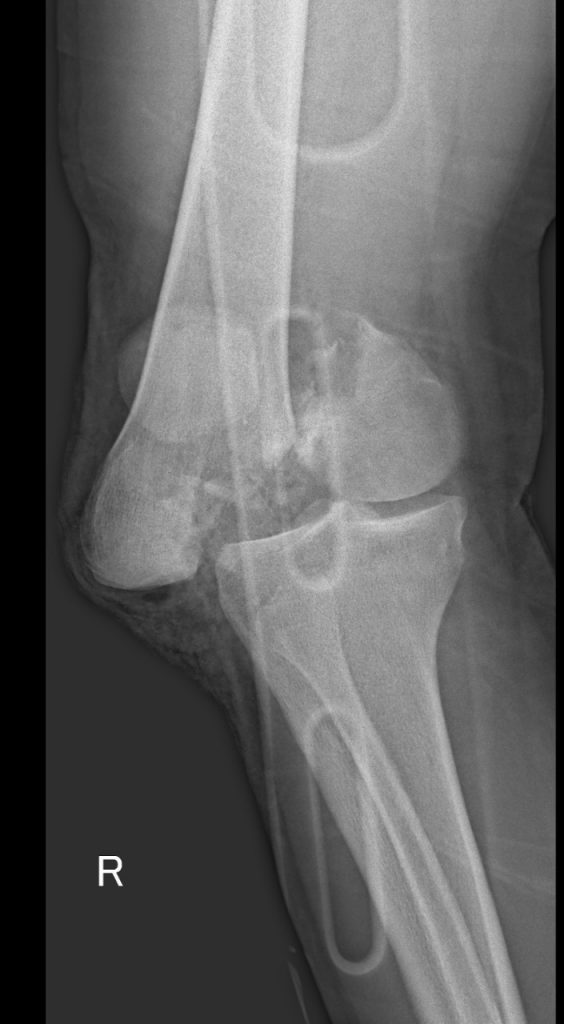

MULTITRAUMA AFTER MOTOR VEHICLE ACCIDENTS

Unfortunately I often see broken bodies after motor vehicle accidents. The injuries sustained are often lifechanging and though the science of orthopedics is advanced, not everything can be repaired to perfection.

Shown here are the x-rays of a young patient who drove at night after taking a few drinks. The fractures are all open and this will be a life changing event for him.